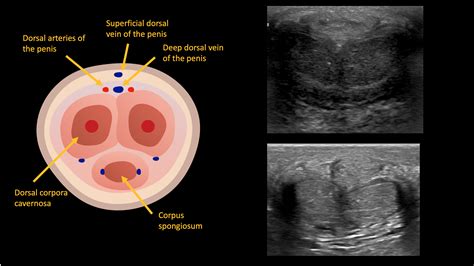

To accurately interpret imaging studies, one must have a granular understanding of the soft tissue compartments of the penis. The organ is primarily composed of three cylindrical bodies wrapped in a dense fibrous sheath known as the tunica albuginea.

• Corpora Cavernosa: These are the two primary erectile cylinders located dorsally. On MRI, they appear as symmetric structures with intermediate signal intensity.

• Corpus Spongiosum: Located ventrally, this structure houses the urethra. It typically demonstrates a slightly different signal intensity compared to the corpora cavernosa, particularly on T2-weighted imaging.

• Tunica Albuginea: This robust layer of connective tissue is crucial in radiology. Its integrity is the primary focus when assessing for penile fractures. In MRI, it appears as a distinct, low-signal intensity (dark) rim surrounding the corpora cavernosa.

High-frequency ultrasound is the preferred modality for initial evaluation, especially in cases of suspected Peyronie’s disease or vascular-related erectile dysfunction. Color Doppler ultrasound allows for the assessment of blood flow within the cavernosal arteries, which is vital for diagnosing venous leak or arterial insufficiency.